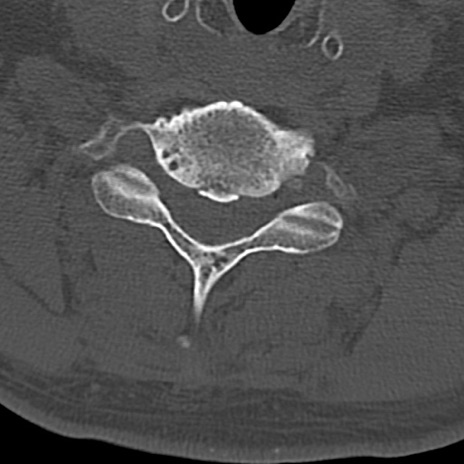

頚椎CT

横断像